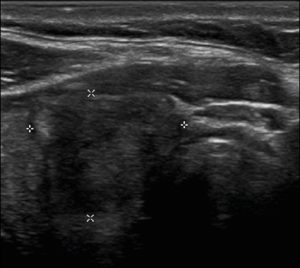

Ở đây, chúng tôi cung cấp các ví dụ minh họa việc áp dụng thực tế hệ thống ACR TI-RADS (Hình 18, 19, 20, 21). Các chú thích dưới hình mô tả chi tiết các mục đã được đánh giá và hiển thị điểm số trong ngoặc đơn.

Hình 18. Hình ảnh nhân giáp dạng đặc (2 điểm), đồng âm (1 điểm), rộng hơn cao (0 điểm), có bờ trơn láng (0 điểm) và không có các ổ tăng âm hay bóng lưng (0 điểm). Do đó, tổng điểm là 3 điểm và mức độ nguy cơ được phân loại là TR3.